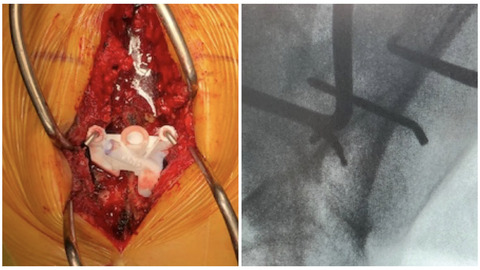

初回でしたので、それなりに展開したのですが、実際は「おもったほど展開しなくてもよかった」というのが感想でした。

わたしは通常、SAIを打つときはtear drop像を確認しながら行っています。

今回もガイドがうまくフィッティングしないときに備えて、術前にtear dropを確認して手術に望みました。

ガイドを乗っけてみると、ピタリと収まりました。

仙骨は腰椎の椎間関節と違って変形があんまりないことが要因と思われます。

4cmくらい下穴をほって、仙腸関節にいくかいかないかくらいでいったんガイドにフィーラーを差し込んで、tear dropで確認することにしました。

するとどうでしょう!!

フィーラーの先端が、tear dropのど真ん中にあるではありませんか!!

久しぶりに鳥肌ものの感動を覚えました。

SAIスクリューを刺入してロッド連結も一直線にいきました!

期待以上で、俊逸すぎました!!

ただ、メダクタには中空のSAIスクリューがないため、ジョンジョンのエクスペディウムを使いました。

そこは、メダクタ、がんばってください!!笑